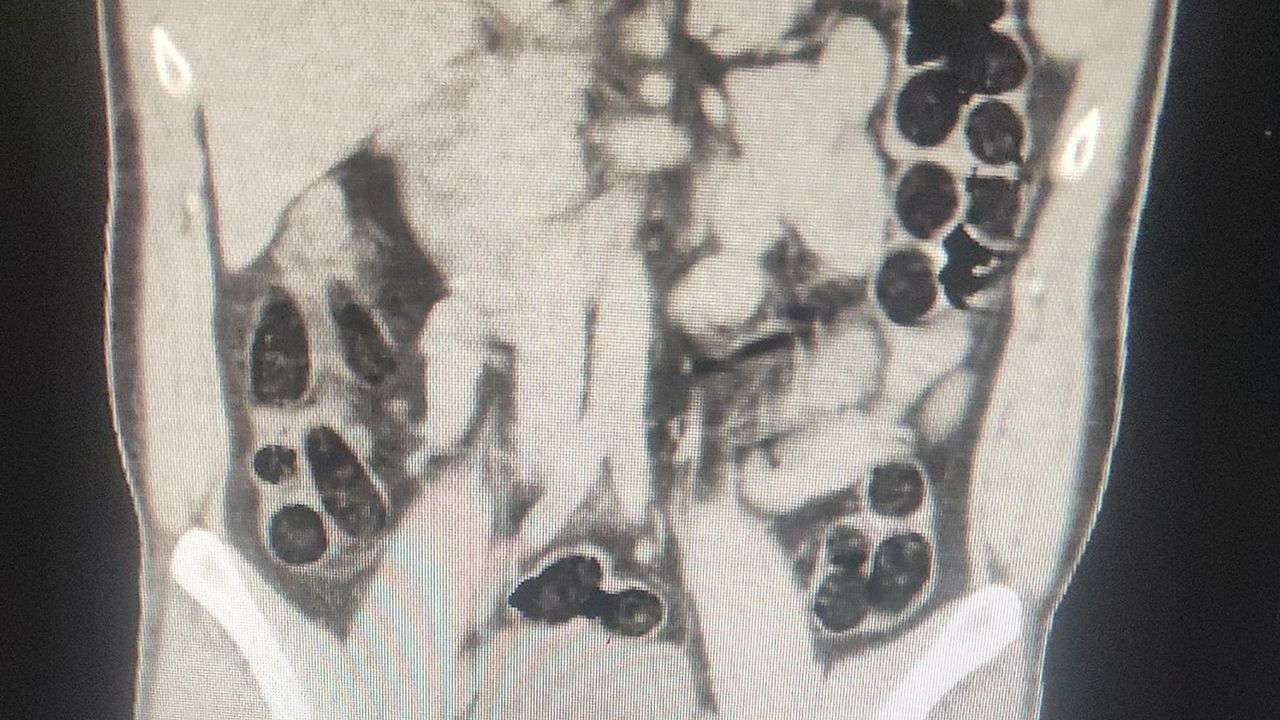

uyruklu şahsın yapılan kontrollerinde ve iç beden muayenesi sonucunda,

şahıslardan birinin midesinde 76 paket halinde, 714 gram eroin maddesi ele

geçirildiği belirtildi.